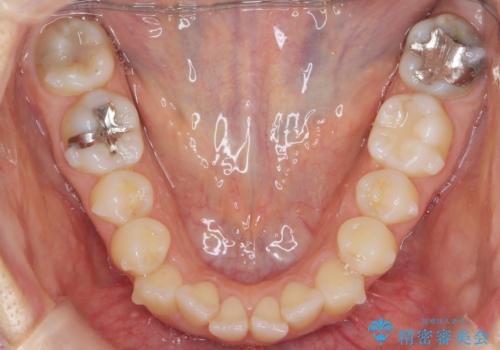

- 気になる前歯のガタつきをマウスピースで治療したいと希望され来院されました。

当日に矯正検査を行い、骨格・歯に問題がないことを確認しマウスピースによる矯正治療を進めます。

IPRを前歯部に少量行うことで、非抜歯でも前歯が外に飛び出さない仕上がりを達成できました。